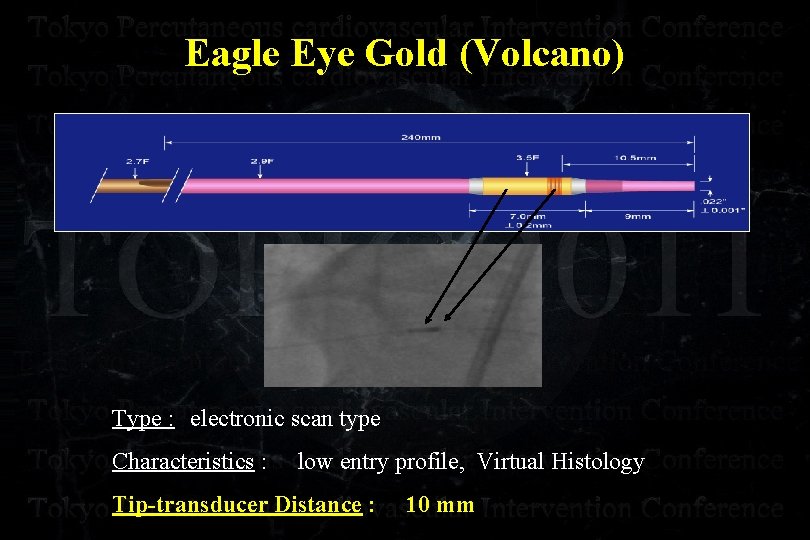

Eagle Eye Gold (Volcano) Type : electronic scan type Characteristics : low entry profile, Virtual Histology Tip-transducer Distance : 10 mm